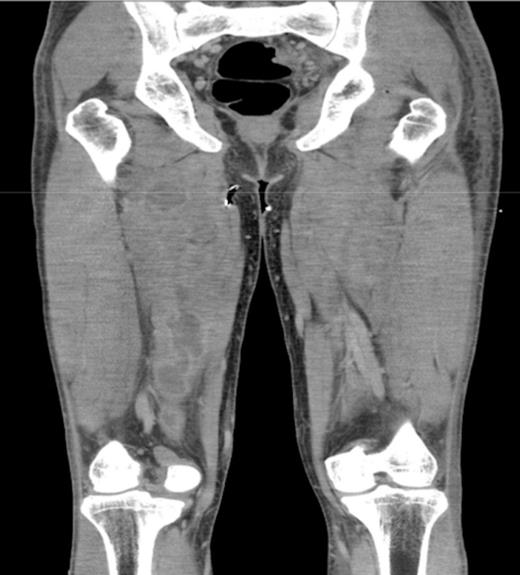

A 31 year old, otherwise healthy young man presented to our emergency department with muscle ache of his legs, a sore throat and fever. Physical examination showed subfebrile temperature, pain of both upper legs and buttocks, but no local inflammation or swelling was noticed. Laboratory examination showed slightly elevated levels of CoReactive Protein (CRP), white blood count (WBC) and Creatine Kinase (CK). The PCR for H1N1 tested positive. With the diagnosis “swine flu” the patient was admitted to the department of internal medicine and therefore oseltamivir treatment was started. However this treatment rendered no success, since the pain increased and spread to both legs and arms. Laboratory findings showed a further increase of both CRP and WBC. The subsequent CT-scan showed multiple abscesses (fig. 1, 2) in the psoas muscle, in both legs and arms. Subsequently 21 abscesses were drained, both surgically and radiologically. All wound and blood cultures showed Staphylococcus aureus, MRSA and PV negative. Our patient was also treated with intravenous flucloxacilline and rifampicine. The patient healed without destruction of muscles.

Diagnosing pyomyositis may be challenging, due to the vague presentation in stage I. Therefore it is often diagnosed with some delay. When the symptoms become more outspoken, apart from history and physical examination, imaging studies are usefull. CT-scan and ultrasound are used to detect abscesses. MRI is the diagnostic tool of choice, because it can detect affected muscles in an early stage. Also more abscesses can be found at unexpected sites, especially when the patient is not responding to treatment. Multifocal abscesses are rare. But, as with our patient, it is of great importance to scan the entire body to detect other abscesses in unexpected regions, if a patient does not respond adequately to the initial treatment.